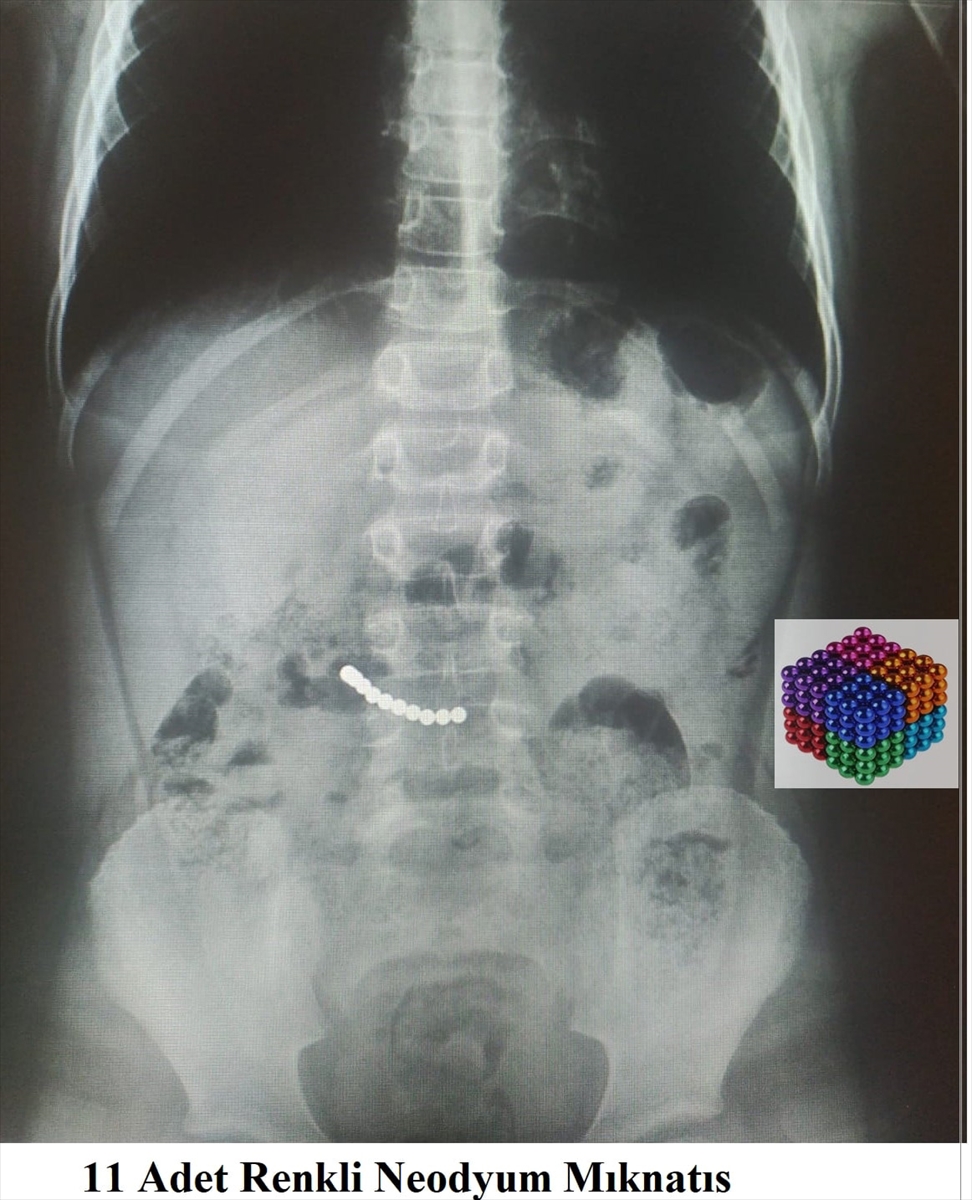

Karın ağrısı şikayetiyle hastaneye götürülen çocuk ameliyata alındı. Çocuğun midesinden tam 11 adet mıknatıs çıkarıldı.

Karın ağrısı şikayetiyle Muğla Eğitim ve Araştırma Hastanesine başvuran 7 yaşındaki U.K'nın kontrollerinde midesinde mıknatıs olduğu belirlendi.

Yaklaşık iki saat süren operasyonla çocuğun midesindeki 11 mıknatıs çıkarıldı.